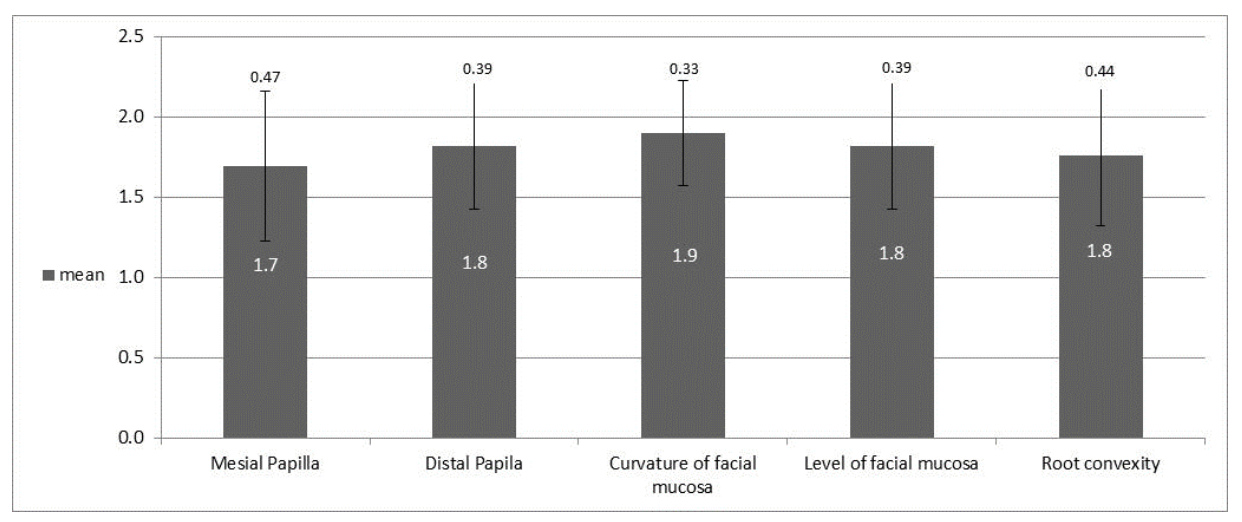

- The presence/absence of mesial papillae

- The presence/absence of the distal papillae

- Curvature contours of the buccal gums

- Height of the buccal gums

- Root convexity/color and soft tissue texture in the buccal aspect of the implant site [15].

3.3. Analysis of Esthetic Results by Index: PES

| Mean | 1.7 | 1.8 | 1.9 | 1.8 | 1.8 | 9 | 1.8 | 1.8 | 1.8 | 1.7 | 1.8 | 8.8 | 17.8 | |